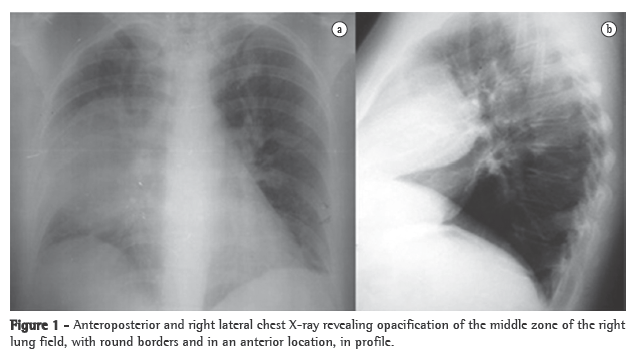

Another chest X-ray, performed on postadmission day 8, showed that the opacity described above persisted. Subsequently, a CT scan of the chest, performed to clarify this issue, revealed a solid formation in the anterior mediastinum. The formation measured 10 cm in its largest diameter and maintained cleavage planes with the heart and the lung, as well as insinuating itself between the lung lobes and compressing them. In addition, a magnetic resonance imaging scan was performed to determine the true extent of the lesion, especially in terms of the cleavage plane with the mediastinal structures (Figure 2), and the findings confirmed those of the CT images.

The patient was then referred for surgery, which allowed the excision of an anterior mediastinal mass (measuring 12 × 9 cm and weighing 400 g), well delineated by a capsule, and whose histology corresponded to ectopic thyroid tissue, the morphology overlapping with that of nodular thyroid hyperplasia but differing from it by presenting microfollicles containing colloid as well as an adjacent inflammatory reaction (Figure 2).